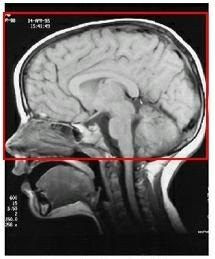

Figure 3. Spatially selective IR pulse inverts arterial spins

Table 2. Image legend

NumberDescription

1Arterial blood flowing into brain

2Spatially selective inversion pulse

3Inverted spins

4Brain tissue

5Venous outflow